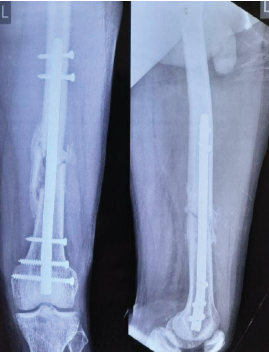

Figure 3: Anteroposterior and lateral views at 3 months showing distal third fracture of femur with retrograde nail.

Out of all study participants, 58 patients had closed fractures and rest 2 patients had compound fractures. The mean operation-injury interval was 5.5 ± 0.67 days for antegrade nailing and 5.8 ± 0.65 days for retrograde nailing. The mean duration of the surgery was 85 ± 2.15 min for retrograde nailing and 95 ± 1.39 min for antegrade nailing. Mean time for radiological union with retrograde nailing was 10 ± 0.38 weeks (Fig. 1, 2, 3, 4) and with antegrade nailing, it was 14 0.44 weeks (Fig. 5, 6).